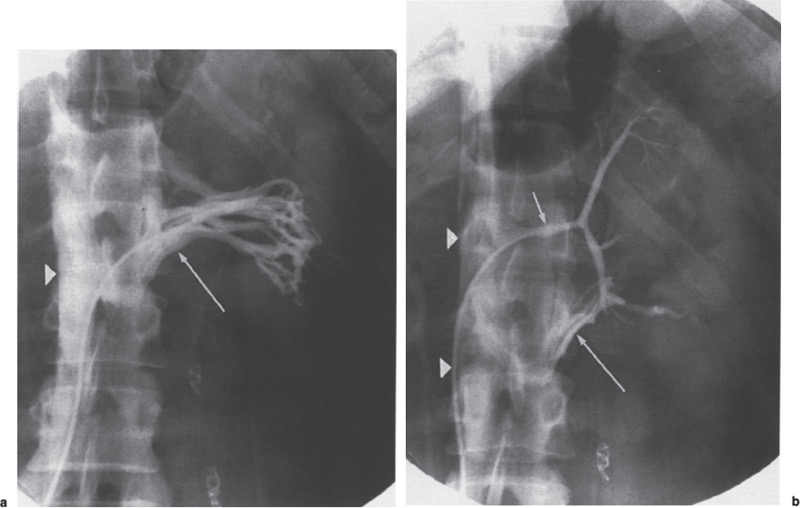

• وایر نازک وارد ورید میشود و تحت فلوروسکوپی به IVC هدایت میشود. - ونوگرافی (Cavography):

• کاتتر چندسوره وارد میشود.

• ماده حاجب تزریق میشود تا آناتومی IVC، قطر آن، موقعیت وریدهای کلیوی (renal veins) و وجود لخته بررسی شود.

• موقعیت ایدهآل فیلتر: درست زیر وریدهای کلیوی (infrarenal) برای جلوگیری از انسداد

- قرارگیری suprarenal (بالای وریدهای کلیوی): در بارداری، ترومبوز infrarenal یا آناتومی غیرعادی.

- خونریزی محل دسترسی، عفونت، malposition، tilt، migration اولیه.